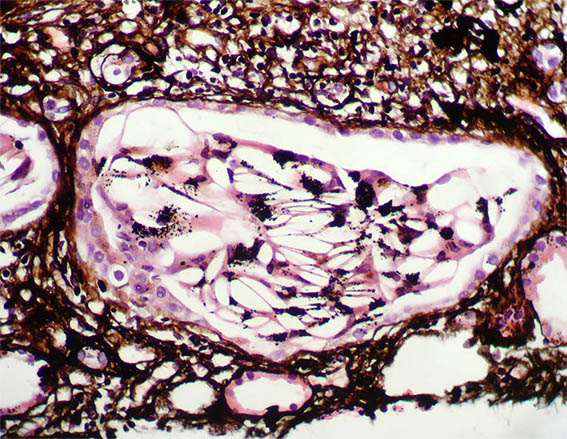

Figura 8. H&E, X400.

Figura 9. H&E, X400.

Figura 10. Tricrómico de Masson, X400.